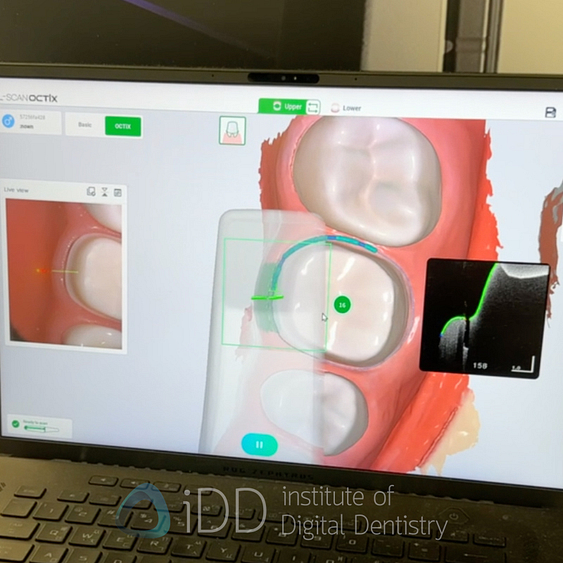

Lilivis - OCT Scanning Technology

Lilivis delivered one of the most surprising innovations at IDS 2025 with the unveiling of their prototype OCTIX scanner, which utilizes Optical Coherence Tomography (OCT) technology rather than conventional intraoral scanning methods.

Unlike traditional intraoral scanners that capture only surface data, this approach enables visualization through tissues - reportedly up to 0.5-1mm through enamel and through gingival margins. This capability could transform restorative dentistry by allowing clinicians to see subgingival margins, detect early caries beneath seemingly intact enamel, and allow for the measurement of enamel thickness.

Although it is a prototype for now, and when I tried it, it was quite slow, it is a fascinating approach to intraoral scanning. I will be watching this closely to see how it develops over the years. This technology represents a potentially disruptive advancement in digital impression technology.

If Lilivis can successfully bring this product to market with the capabilities demonstrated, it could address some of the most persistent issues clinicians have with digital impressions - particularly visualization of deep subgingival margins and detection of conditions beneath intact tooth surfaces.